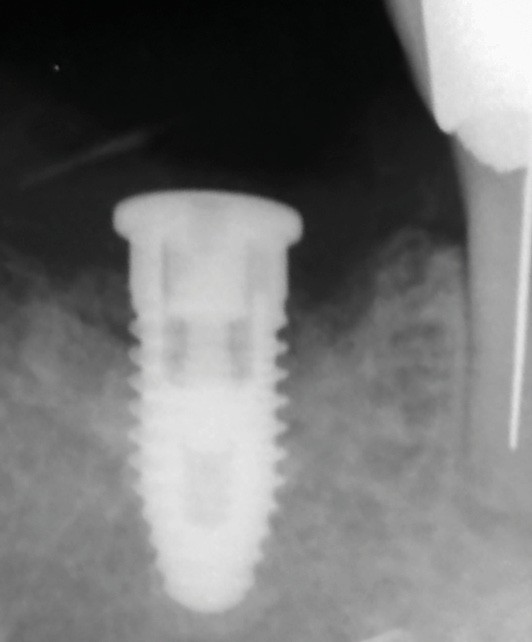

La patiente est restée 4 semaines sans couronne. Après l’intervention chirurgicale, elle a entamé un programme de soins péri-implantaires et parodontaux, avec des visites de rappel tous les 4 mois.

Dans les cas de traitement de péri-implantite, un suivi d’un an est considéré comme un suivi court. Néanmoins, le cas présent est stable après un an et ne présente aucun signe de récidive. Des contrôles supplémentaires sont nécessaires.